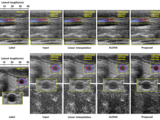

Efficient B-mode Ultrasound Image Reconstruction Using CNN

Yoon, Yeo Hun, Shujaat Khan, Jaeyoung Huh, and Jong Chul Ye. "Efficient B-mode Ultrasound Image Reconstruction from Sub-sampled RF Data using Deep Learning." IEEE transactions on medical imaging (2018).